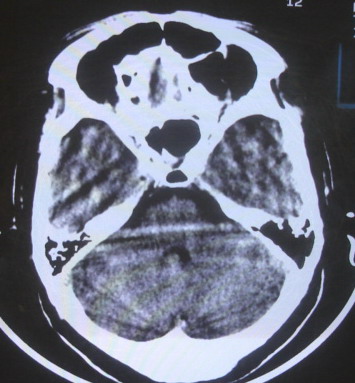

女  67岁 双下肢无力,行动不灵便

脑萎缩,腔隙性脑梗塞.

双侧额桥束及左侧脑室旁多发腔梗塞+老年性脑改变

多发腔梗、老年性脑改变、脑白质异常。